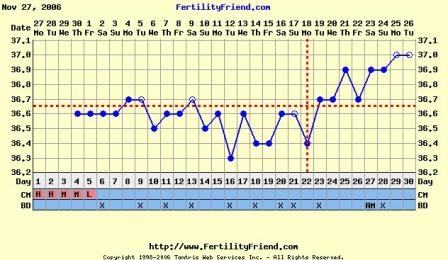

Nem tudom, hogy ez normális-e, miközben minden hormonom rendben, és a hőgörbe mutat pé-t. Meg van pozitív LH tesztem is...

Gaby: a Te görbéd elég cikkcakkos, szerintem később pé-zel...Végülis hathatott a párodnál már a gyógyszer, ha nem is drasztikusan, de már jobbak lehetnek az eredményei...